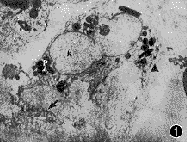

1.足突细胞特征:16例标本中,9例患者的视网膜表面膜组织中可见一种细胞边缘伸出大量足突(lamellipodia)的细胞,这些足突长短不一,或卷曲或伸直,并和细胞外纤维状胶原接触(图1~3)。足突细胞的外形主要呈现两种类型:(1)肾形或不规则形,胞浆内常有丰富的色素颗粒;(2)为长肾形(梭形),基本不含色素颗粒。这两种类型的细胞胞浆内细胞器异常丰富,在梭形性细胞中微丝更明显。在有色素颗粒的细胞周围,可见纤维性胶原分布,但是在每个细胞周围的分布程度有差别,无色素颗粒细胞周围胶原分布无规律,可以很丰富,也可能缺乏。

图1~3 带有色素颗粒的肾形足突细胞,可见一长足突(箭头示)和短足突(▲),P示色素颗粒,N示细胞核 ×9 000